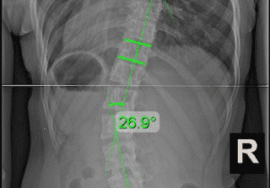

- اعوجاج العمود الفقري (انحناء جانبي)

كيفية تشخيص أي مشكلة في العمود الفقري

عند زيارة الطبيب، يتم:

- فحص القوام والظهر

- تقييم التماثل بين الجانبين

- اختبار الانحناء

- طلب أشعة لتحديد درجة الانحناء عند الحاجة

الاعوجاج حالة مستمرة ولهذا السب قد تحتاج تدخلًا في مراحل مختلفة من العمر. وبفضل وجود تقنيات التصنيف المعتمدة ، يمكن للأطباء تصميم خطة علاجية مخصصة تضمن تدخلاً جراحيًا عند الضرورة أو العلاج غير الجراحي قبل ذلك، لتفادي الاضطراب في الوظائف التنفسية أو أي أعراض متأخرة. فريقنا المحترف يضم نخبة من الأطباء والمتخصصين الذين يجمعون بين الخبرة والاحترافية لتقديم خطة علاجية غيرر جراحيه شاملة ومخصصة لحالتك، تضمن السيطرة على الانحناء ومنع زيادته.

لا تسمح لاعوجاج العمود الفقري بأن يؤثر على صحتك أو يسبب مضاعفات مستقبلية خطيرة،. مع مركز الرواد، أنت في أيدٍ أمينة، نعتمد على أحدث الأساليب العالمية لتصنيف الحالة ووضع خطة علاج دقيقة تناسب كل مرحلة عمرية.